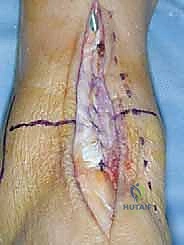

1. الشق الجراحي والوصول للمفصل

يقوم الجراح بإجراء شق أمامي طولي (Anterior Approach) في منتصف الكاحل. يتم إبعاد الأوتار والأوعية الدموية والأعصاب بعناية فائقة (هنا تتجلى أهمية مهارات الجراحة الدقيقة التي يمتلكها الدكتور هطيف) للوصول إلى محفظة المفصل.